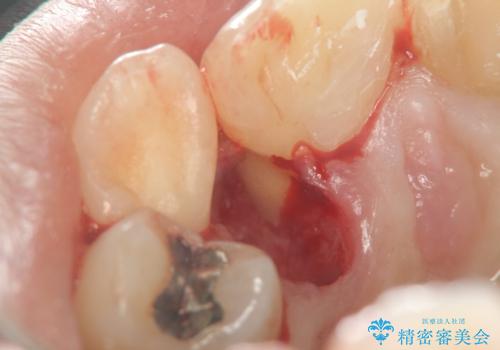

歯根の近接のみられる右上側切歯を抜去し、根管治療を伴うセラミック治療を計画します。

歯根近接について

叢生が著しく、歯根の近接が見られる場合歯磨きができず歯石がたまりやすく骨吸収の原因となることが多いです。

このような場合矯正や転位歯の抜去が治療方法として挙げられます。